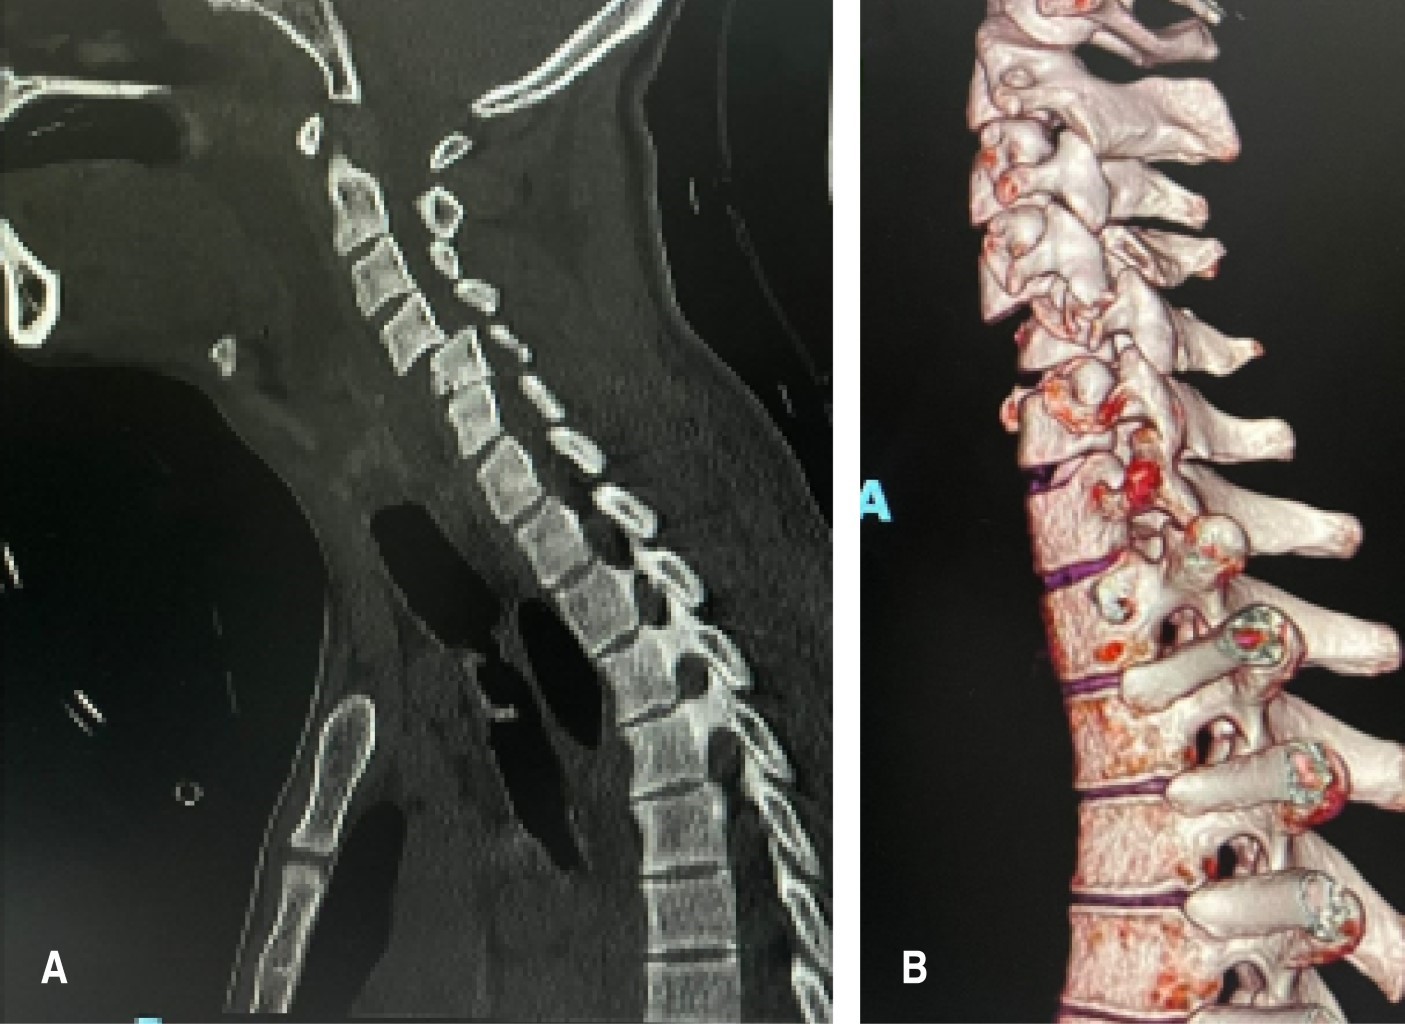

Posterior a la adecuada instauración del apoyo vital avanzado en trauma (ATLS), los pacientes con sospecha de traumatismo cervical subaxial deberán someterse a pruebas de detección por imagen. Siendo de manera inicial necesarias las proyecciones radiográficas en posición anteroposterior, lateral y transoral para la evaluación de la columna cervical, abarcando desde la unión craneocervical hasta la primer torácica, obteniendo una visualización clara de la unión cervicotorácica, ya que las fracturas de C7 y la fractura-luxación de C7-T1 representan casi 17% de las lesiones de la columna cervical. Se deberá prestar atención en la alineación de la columna cervical, altura del disco o cambios en las distancias interespinosas. A pesar de ser un estudio práctico y accesible, recientes estudios han demostrado que la radiografía simple tiene sólo apenas entre 30 y 60% de sensibilidad para evaluar lesiones y fracturas a este nivel. El uso de proyecciones en flexión-extensión para evaluar la estabilidad de los ligamentos se ha cuestionado por la dificultad de la obtención y el advenimiento de otros estudios superiores para evaluar integridad ligamentaria, por lo tanto, son mínimamente útiles en situaciones agudas. La tomografía axial computarizada, considerada como el caballo de batalla de las imágenes traumáticas en la columna, presenta ventajas con respecto al uso de imágenes radiográficas u obtenidas por resonancia magnética, entre las cuales tenemos la facilidad de realización, rapidez, equipos propensos a sufrir menos fallas técnicas, asegurando así una mayor precisión diagnóstica, ya que ofrece una excelente visualización de las uniones cervicotorácica y occipitocervical, que a menudo son de mala calidad en las radiografías simples. En algunos estudios se ha demostrado sensibilidad de 99% y especificidad del 100% con el uso de la tomografía axial computarizada multiplanar. Sin embargo, con la limitante en la identificación de lesiones puramente ligamentarias, en la cual la resonancia magnética cuenta con una alta sensibilidad y especificidad con tasas reportadas de 91 y 100%, respectivamente. Sin embargo, dicho estudio también tiene una alta tasa de falsos positivos; además, los hallazgos positivos en la resonancia magnética sugestivos de lesión ligamentosa en aquellos con resultados negativos por medio de tomografía axial computarizada rara vez requirieron intervención quirúrgica (Figura 1).6-8